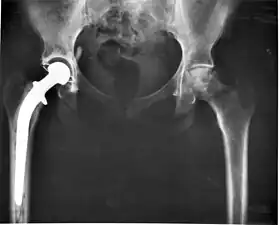

• Class III devices generally require premarket approval (PMA) or premarket notification (510k), a scientific review to ensure the device's safety and effectiveness, in addition to the general controls of Class I. Examples include replacement heart valves, hip and knee joint implants, silicone gel-filled breast implants, implanted cerebellar stimulators, implantable pacemaker pulse generators and endosseous (intra-bone) implants.

Implants, such as artificial hip joints, are generally extensively regulated due to the invasive nature of such devices.